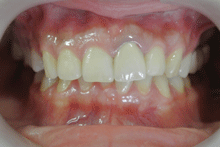

ハイブリッドセラミックス

ハイブリッドセラミックスとはセラミック粒子を92%含有した白い材料で、セラミックスのもつ審美性と耐久性、

より天然歯に近い硬さの材料です。